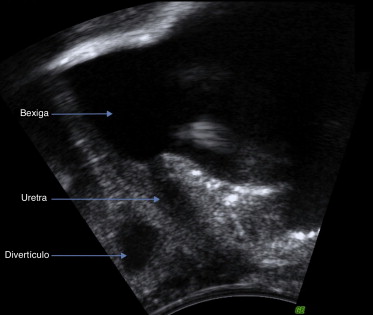

A maioria dos DUF relaciona‐se com a parede média ou distal da uretra12  ;  13 e comunica com a sua parede posterior (ver fig. 1 )16 . Geralmente, são únicos12 ; 23  ;  28 , com apenas um orifício de abertura para a uretra10 e com dimensões entre os 0,2 e os 6 cm13 ; 23 ; 29  ;  30 . Contudo, podem ser múltiplos em 6‐22% dos casos12 ; 23  ;  28 , frequentemente com canais comunicantes finos e friáveis entre si31 . Similarmente, podem apresentar conformações complexas resultantes do seu prolongamento anterior31 : em 10‐38% dos casos apresentam forma de ferradura12 ; 13 ; 23 ; 24 ; 28  ;  29 e em 4‐33% são circunferenciais23 ; 24 ; 28  ;  29 . Ocasionalmente, poderão prolongar‐se proximalmente, relacionando‐se anatomicamente com o colo e trígono vesicais10 .

Imagem ecográfica em plano para‐sagital obtida com sonda transvaginal de ...

Figura 1.

Imagem ecográfica em plano para‐sagital obtida com sonda transvaginal de divertículo da uretra feminino em relação com a parede uretral média posterior.